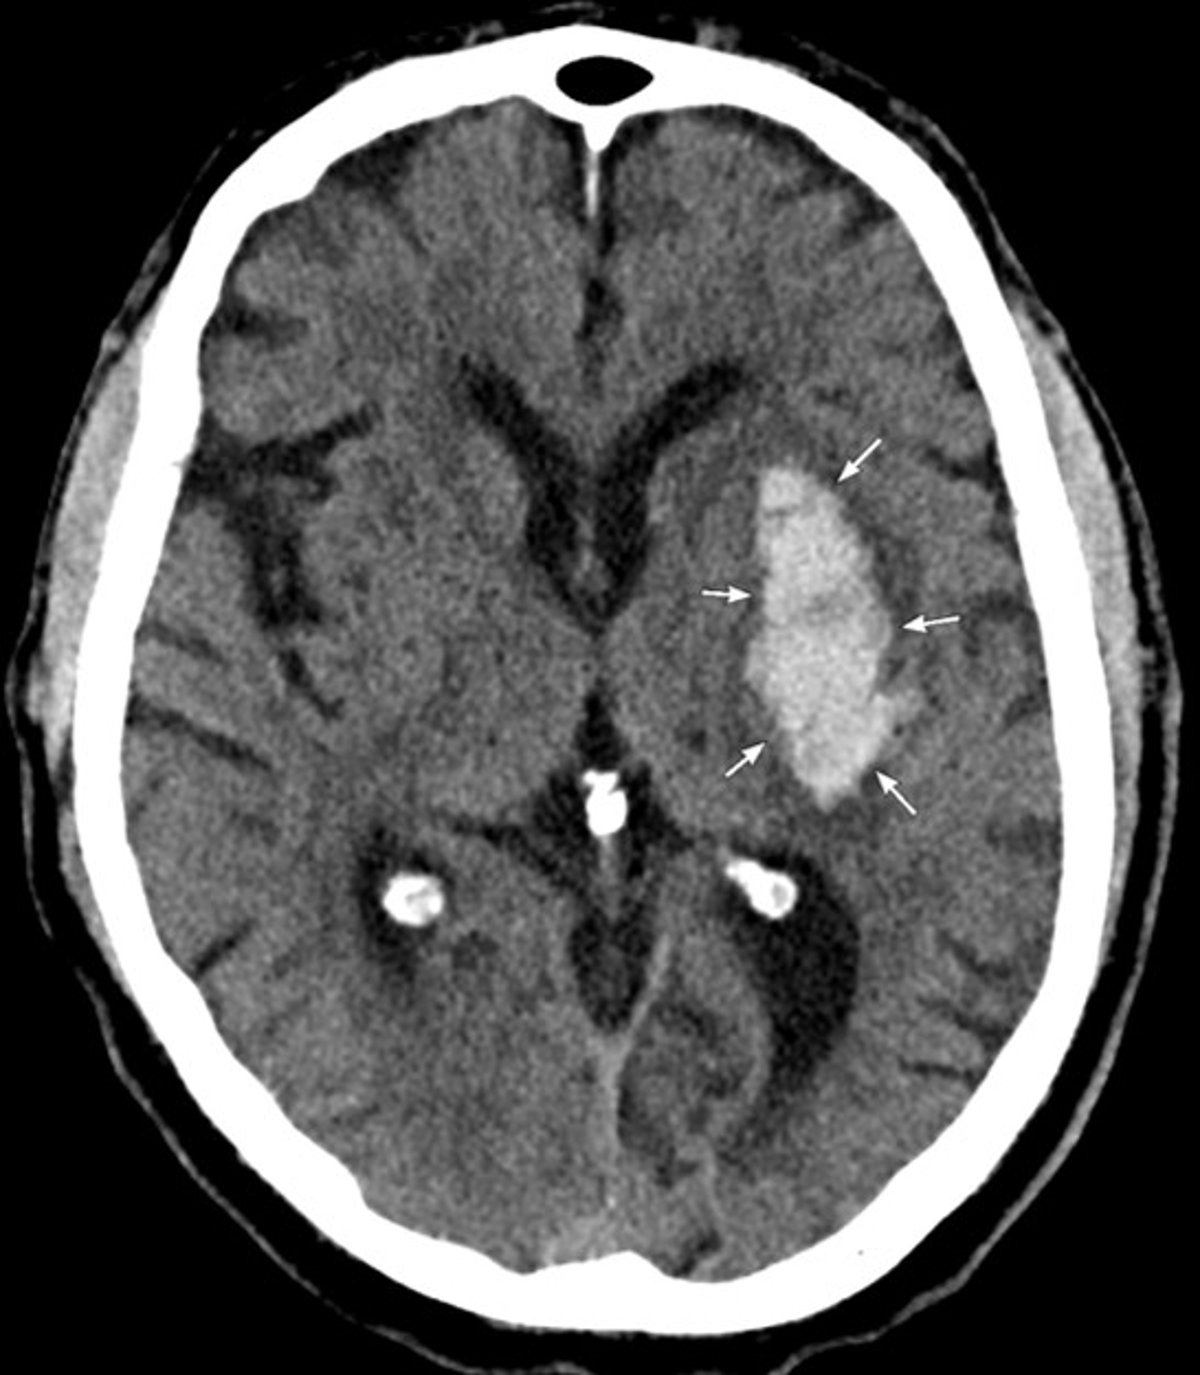

CT of the Head

CT shows an acute hemorrhage in the left basal ganglia that is consistent with hypertensive intracerebral hemorrhage.

Image courtesy of Mustafa Mafraji, MD.